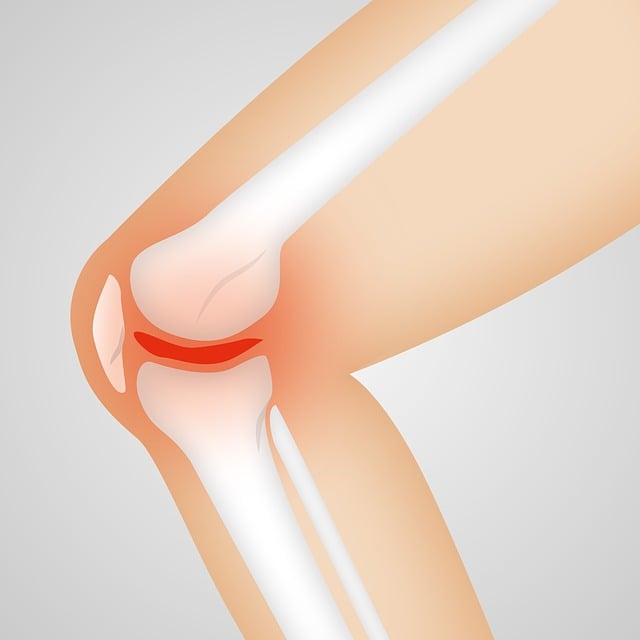

초기의 통풍 증상은 갑작스럽게 나타나는 것이 특징입니다. 통풍 발작은 보통 한밤중에 발생하며, 침범된 관절이 뜨거워지고 붉게 변하며 심한 통증과 부종을 동반합니다. 주로 엄지발가락 관절에서 시작되지만, 발목, 무릎, 손가락 등 다른 관절에서도 발생할 수 있습니다.

또한 통풍 증상인 발작은 몇 시간 내에 극심한 통증을 유발하며, 치료하지 않을 경우 며칠에서 몇 주까지 지속될 수 있습니다. 발작 중에는 관절을 움직이기 힘들며, 피부가 붉어지고 열이 나는 통풍 증상이 나타납니다.